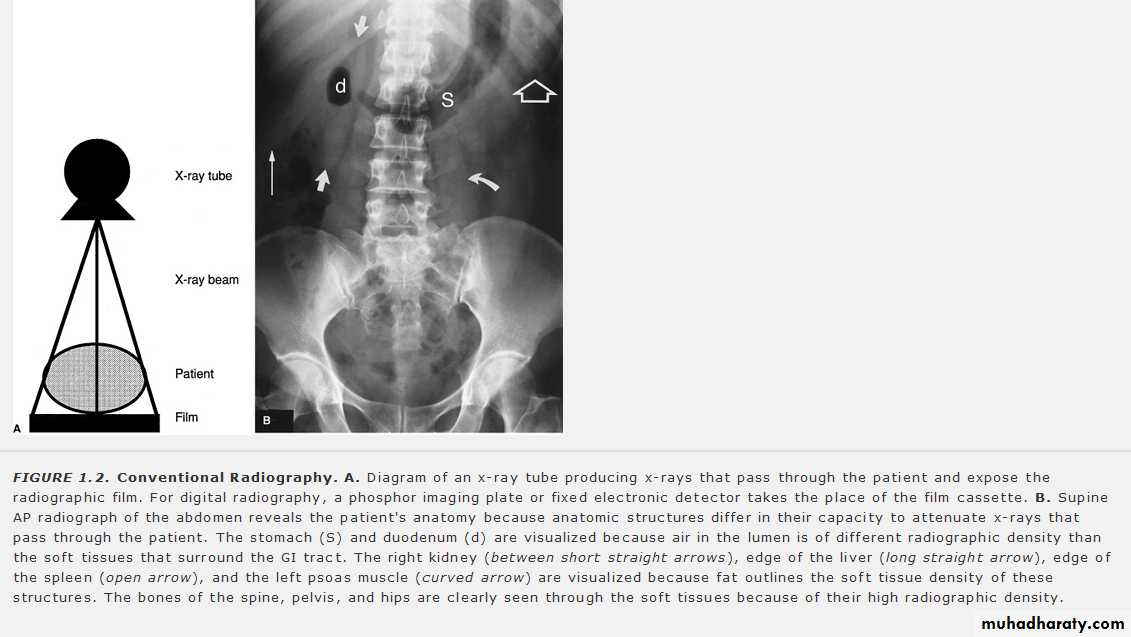

According to x- ray attenuation in the tissues ( x – ray penetration) ,the radiographic appearace can be graded into :

Tranceradiant as gases

Radiolucent or trancelucent as in fatty tissue

Mild radio radio-opague as fluid , muscle ..

Moderate radio-opague as bones and calcifications

Dense radio-opague as metals and contrasts

Radiography ( static ) : Coventional and digital ( CR and DR )